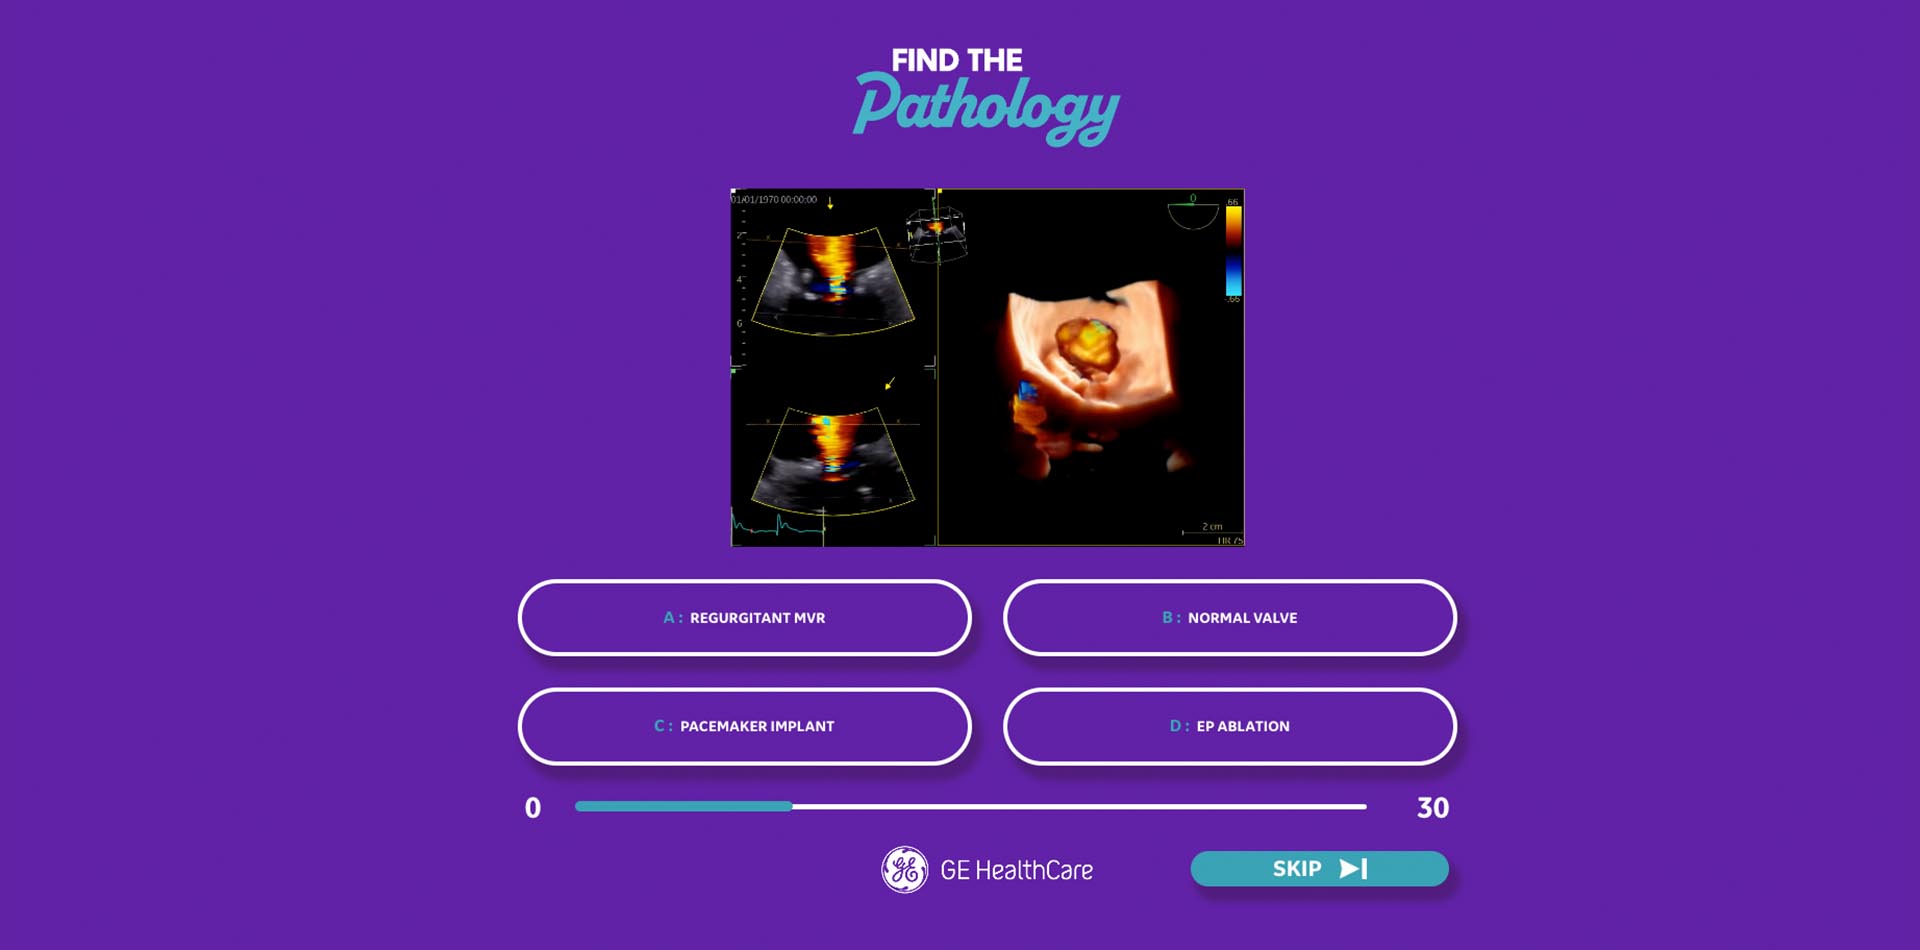

Our creative team worked to find something that would be exciting enough to attract an audience, and would work on the screens available on the stand. It was decided that new games should be developed that played into the audience’s competitive nature.

Using a combination of strategic insight and a creative ideation process, the team at TrunkBBI developed multiple game ideas, from a simple quiz to a more complex ‘Beat the AI’ concept, allowing sonographers to test their skills against a pre-programmed scan in real-time. The intent was for this to showcase the incredible power of GE HealthCare’s machine AI capability, and prove to our audience how it could help reduce scanning time in a busy role.

The concepts worked on multiple levels – continuing with GE HealthCare’s goal of highlighting new ultrasound machine updates, and as a way to engage more fully with BMUS attendees and collect information for follow-up.